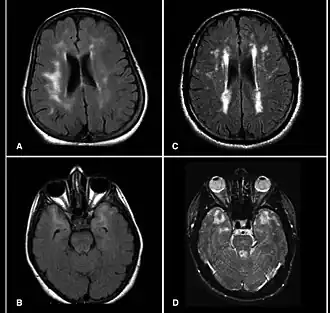

MRI van patiënten met het CADASIL waarin meerdere laesies te zien zijn | ||||

Het CADASIL-syndroom (cerebrale autosomale dominant arteriopathie met subcorticale infarcten en leukencefalopathie) is de meest voorkomende vorm van erfelijke beroertes, en wordt verondersteld veroorzaakt te worden door mutaties van het Notch 3-gen op chromosoom 19.[1]

De aandoening is een vorm van leukodystrofie. De meest voorkomende klinische manifestaties zijn migraine, hoofdpijn en TIA's of beroertes die gemiddeld tussen 40- en 50-jarige leeftijd optreden, hoewel het ook is gevonden in individuen van 20 tot 70 jaar. Met DNA-onderzoek kan de aanwezigheid van de NOTCH-3 variant die CADASIL veroorzaakt worden aangetoond. Dit onderzoek kan ook worden uitgevoerd voor de ziekte zich manifesteert.[2]